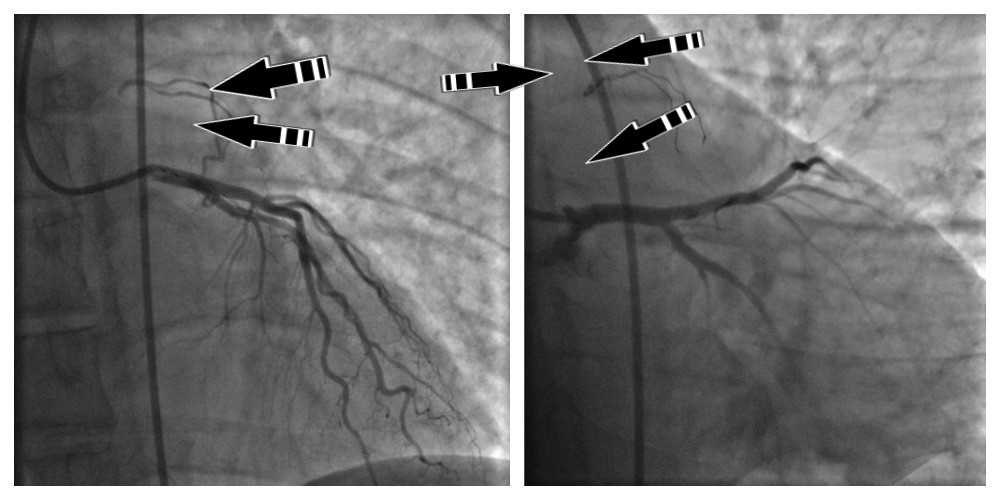

Эндоваскулярная процедура окклюзии корнаро-легочной фистулы выполняется под местной анестезией путем пункции бедренной артерии и катетеризации коронарной ветви. В представленном наблюдении коронаро-легочная фистула находилась в левом коронарном бассейне, поэтому катетеризовался ствол левой коронарной артерии. Выполнялась коронарография, определялся патологический афферент в проксимальной трети ПМЖВ на протяжении 15 см и диаметром не более 1.5 мм (с делением на два ствола в средней трети) и с незначительным венозным сбросом в легочный ствол. С помощью микропроводников и микрокатетера поочередно селективно катетеризированы афференты с последующей эмболизацией микроспиралями. Осложнений в данной манипуляции не наблюдалось. На контрольной коронарограмме достигнута полная эмболизация целевых артерий. По окончании исследования катетер удален с последующим гемостазом зоны пункции и наложением асептической давящей повязки на бедренную артерию.